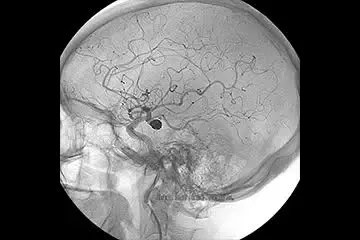

Tindakan Clipping dan Coiling Aneurysm Serta Efek Sampingnya - WeCare.id